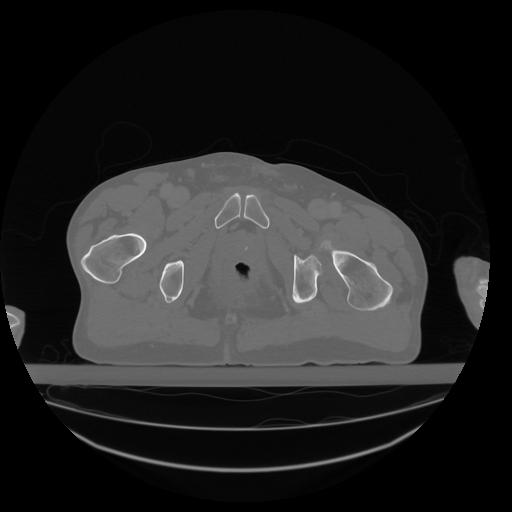

34 CUERPO,CE,Vol,1.0,CUERPO,,